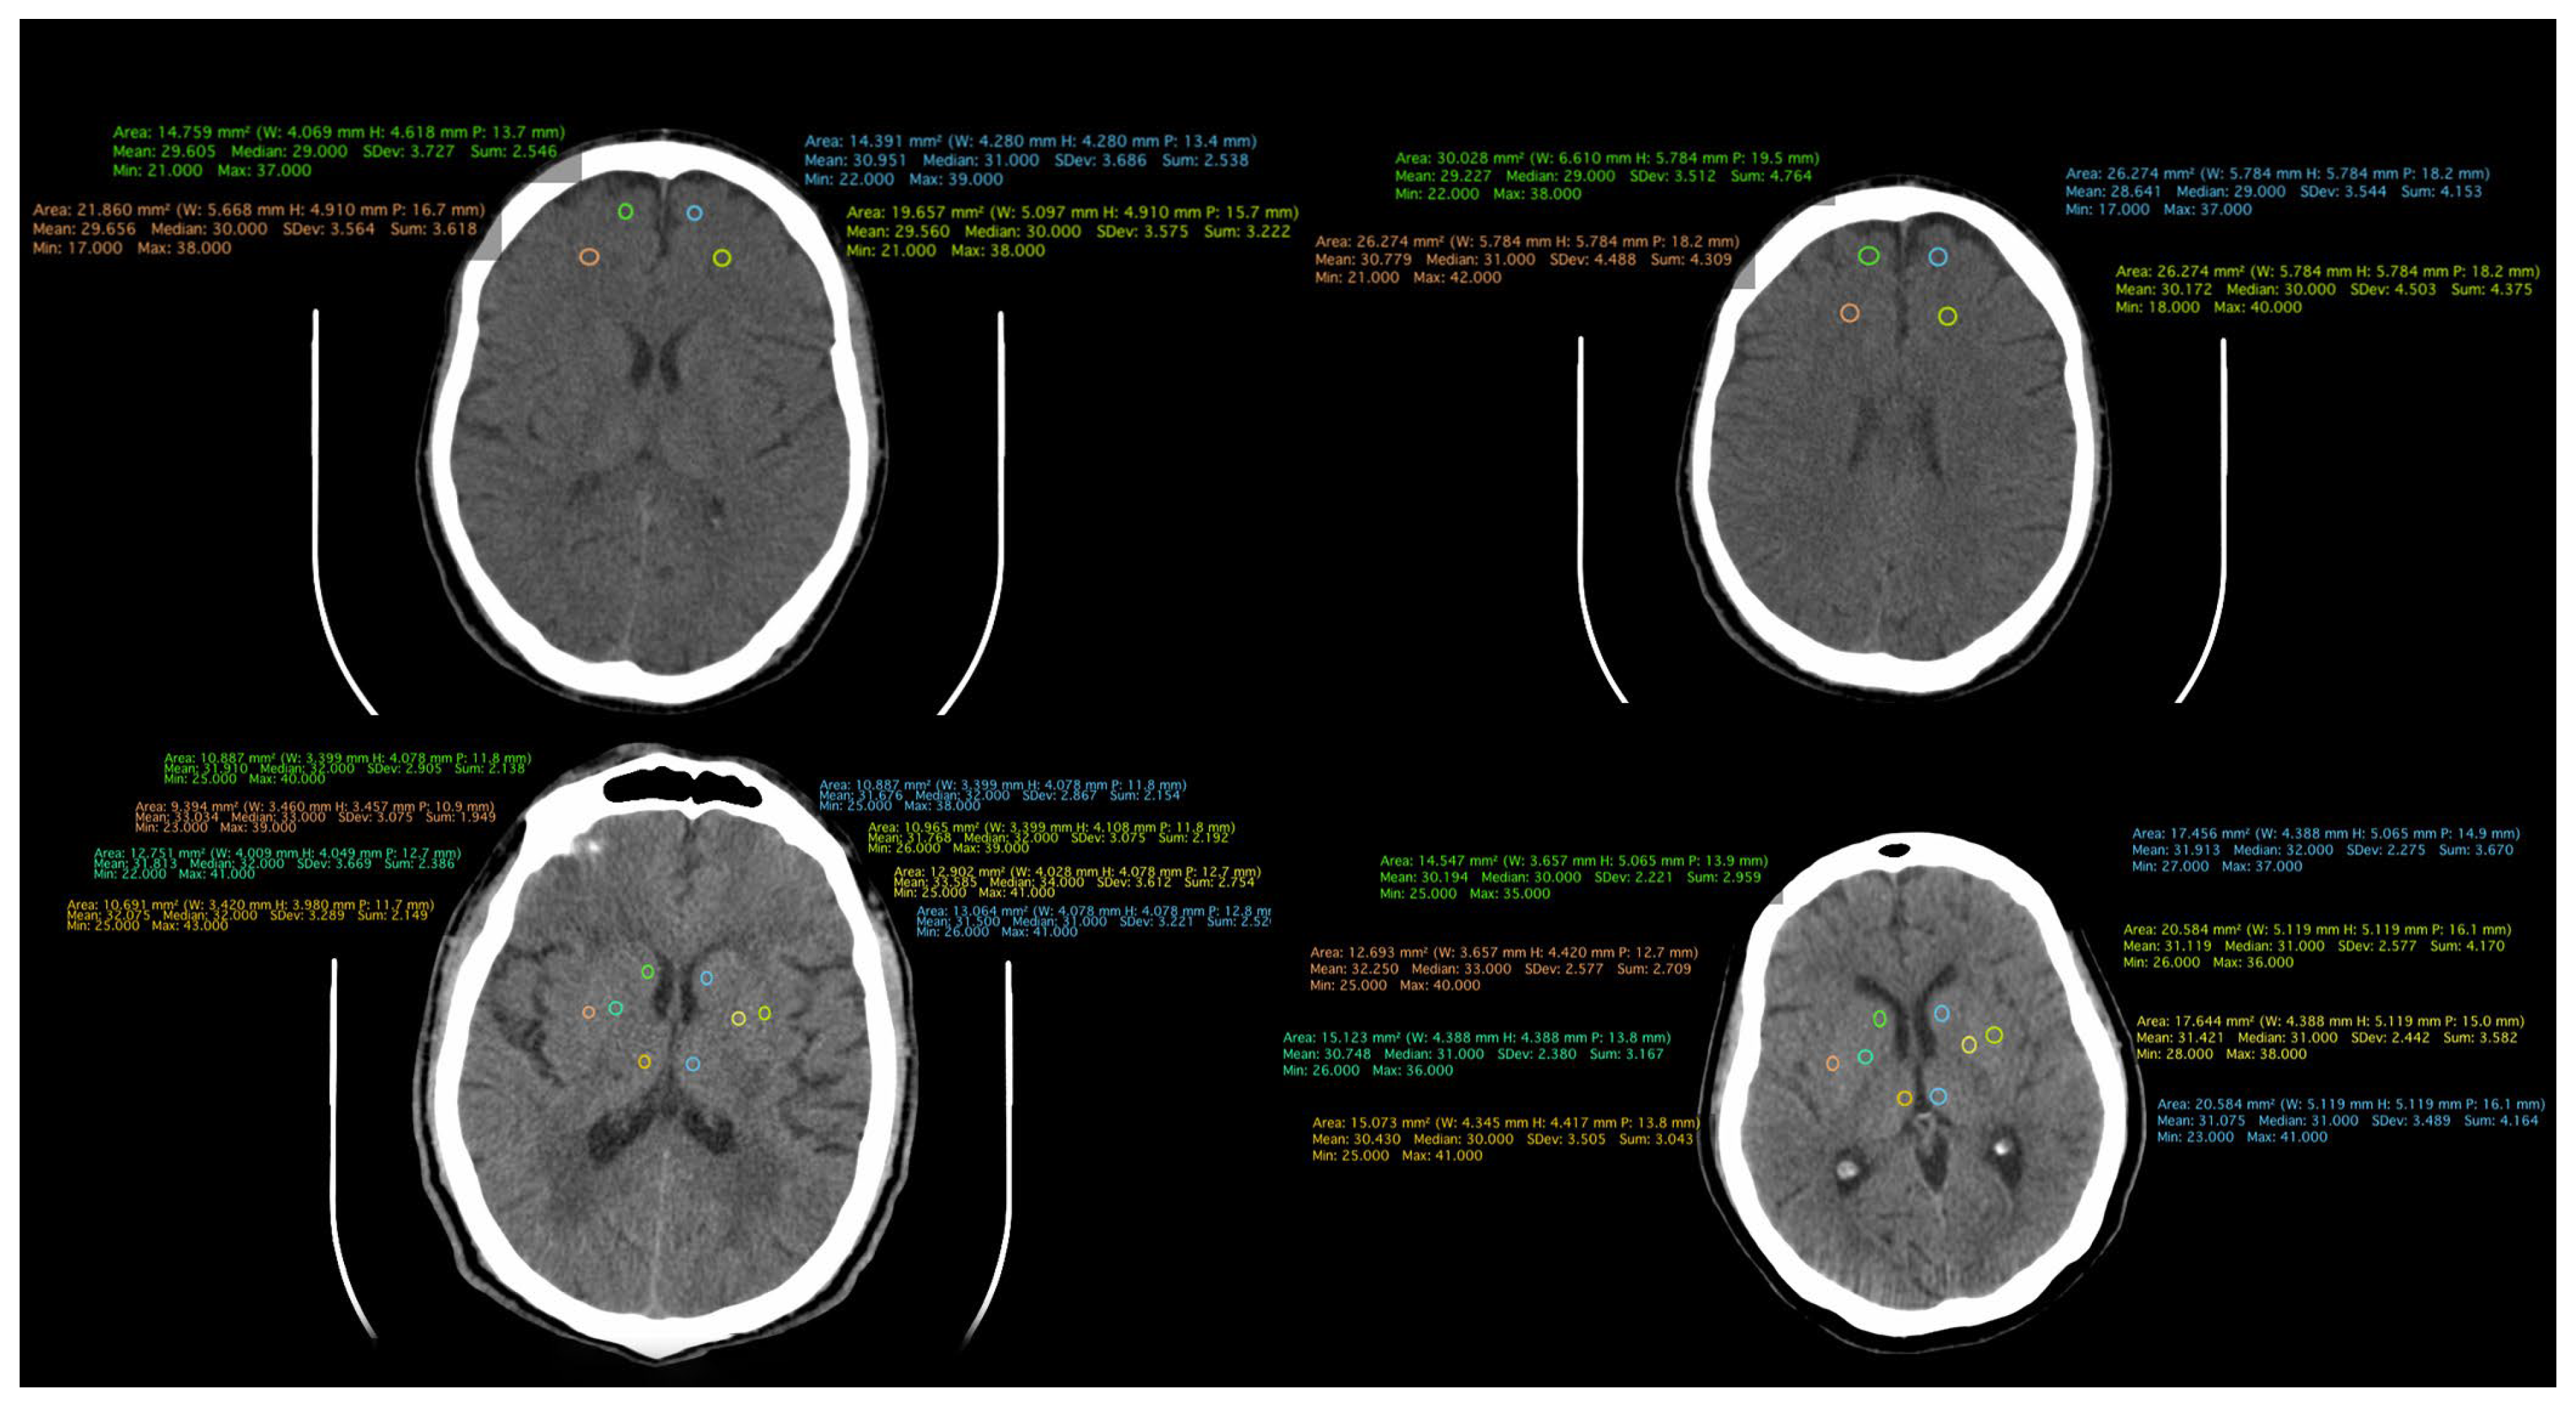

All patient-related information was collected from the paper and electronic patient records. Data were collected by certified medical staff, including board-certified psychiatrists and an imaging specialist. The database included demographic data, information regarding the onset and duration of the illness, the number of episodes, and the type of treatment received. Additionally, information obtained through CT examinations was incorporated, including measurements such as the transverse diameter between the frontal horn tips on axial section, transverse diameter at the level of the lateral ventricle bifurcation at the most cranial point of the ventricle on axial section, transverse diameter at the level of the diencephalic third ventricle on axial section, antero-posterior diameter at the level of the fourth ventricle on axial section, and density measurements in both the anterior and posterior portions of the frontal lobe at the cortical and subcortical levels. (Figure 1, Figure 2 and Figure 3).

Figure 1. CT scan of a patient from the FES group.

The densities of structures in the frontal lobe were measured using cerebral CT explorations. In the cortical region, a higher density is evident in both the anterior right and left portions, as well as in the posterior right portion, in patients with schizophrenia compared to those in the first episode of the illness and those in the control group. As per the cortical area of the left posterior region, the highest density is observed in patients in the FES group. Notably, in the subcortical portion, a higher density is recorded in the anterior left region of the frontal lobe in schizophrenia patients, with the highest densities observed across all other regions in the FES group. The lowest densities across all measured structures were consistently found in the control group (Figure 6). The statistical analysis using the ANOVA test for each structure individually is described in Table 2.